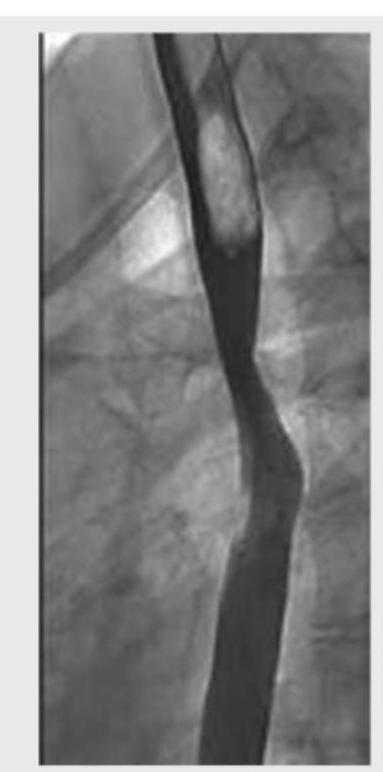

The following barium swallow study shows which of the following?

Explanation: ***Esophageal varices*** - The Barium Swallow image clearly demonstrates a **serpiginous**, worm-like, or **rosary bead-like appearance** along the esophageal wall, which is characteristic of esophageal varices. - Varices are dilated submucosal veins and appear as **filling defects** on barium studies, especially when distended. *Schatzki ring* - A Schatzki ring is a **thin, symmetric mucosal ring** at the esophagogastric junction, causing solid food dysphagia. - It presents as a **smooth, circumferential narrowing** on a barium swallow, which is not seen here. *Candida esophagitis* - Candida esophagitis typically appears as **ulcerations, plaques, or nodularity** with an irregular, cobblestone pattern on barium swallow. - This image does not show the characteristic **"shaggy" or "cobblestone"** appearance associated with candidal plaques. *Reflux esophagitis* - Reflux esophagitis can manifest as **mucosal irregularity, erosions, or strictures**, but not the distinct serpiginous filling defects seen in this image. - Severe reflux can cause peptic strictures, which appear as **smooth, tapered narrowings**, different from the irregular variceal pattern.